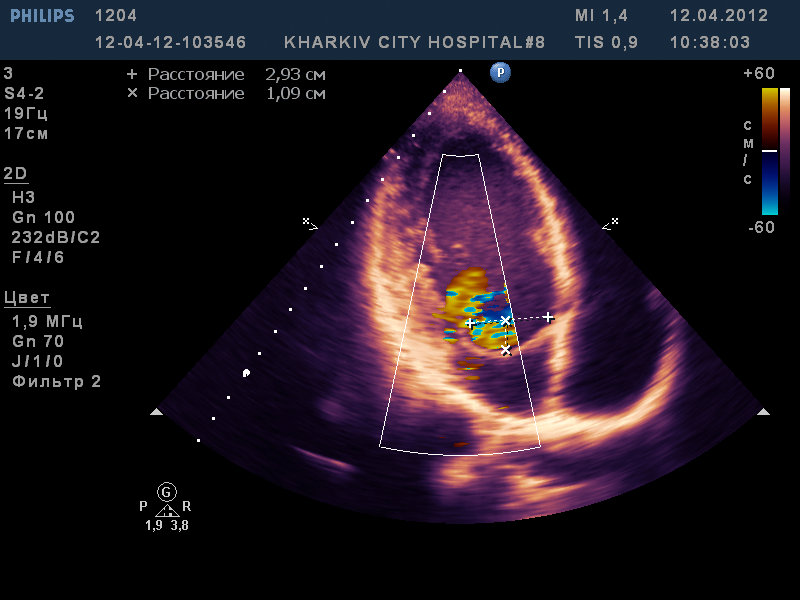

Парень 22 лет/

двухстворчатый аортальный клапан с выраженной аортальной недостаточностью, расширение восходящего отдела аорты до 4,2см, пролабирование передней створки МК III степени с незначительной регургитацией, дилатация левых полостей (КДР 6,6 КСР 4,5 ЛП 4,2), гипертрофия левого желудочка.

На видео видно двухстворчатый аортальный клапан с неполным смыканием створки с выраженной регургитацией (высокоскоростная струя под углом ударяет в переднюю створку митрального клапана вызывая пролабирование).